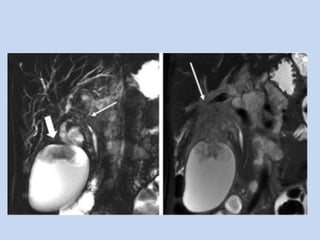

• In pancreatic divisum :

- occurs in 5.5 – 7.5% individuals

- MC variant of pancreatic duct, where the dorsal &

ventral anlage of the pancreas fail to fuse – resulting

in two separate drainage routes for pancreatic

secretions.

APPLICATIONS • In pancreaticdivisum : - occurs in 5.5 – 7.5% individuals - MC variant of pancreatic duct, where the dorsal & ventral anlage of the pancreas fail to fuse – resulting in two separate drainage routes for pancreatic secretions.